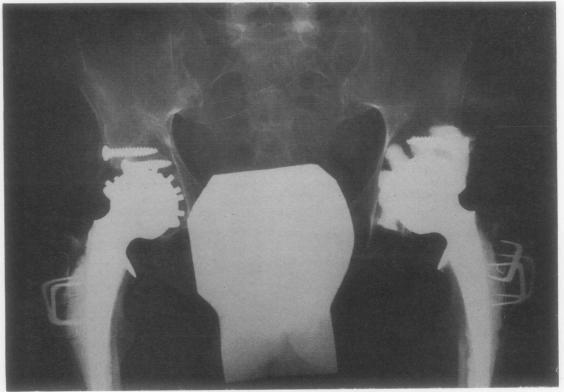

Total hip replacement using the McKee-Farrar prosthesis. In rheumatoid arthritis, Still's disease, and ankylosing spondylitis.

Ann Rheum Dis. 1970 Jan;29(1):1-5. doi: 10.1136/ard.29.1.1.

https://cdn.ncbi.nlm.nih.gov/pmc/blobs/c162/1031214/6fc8f63f0318/annrheumd00240-0010-a.jpg